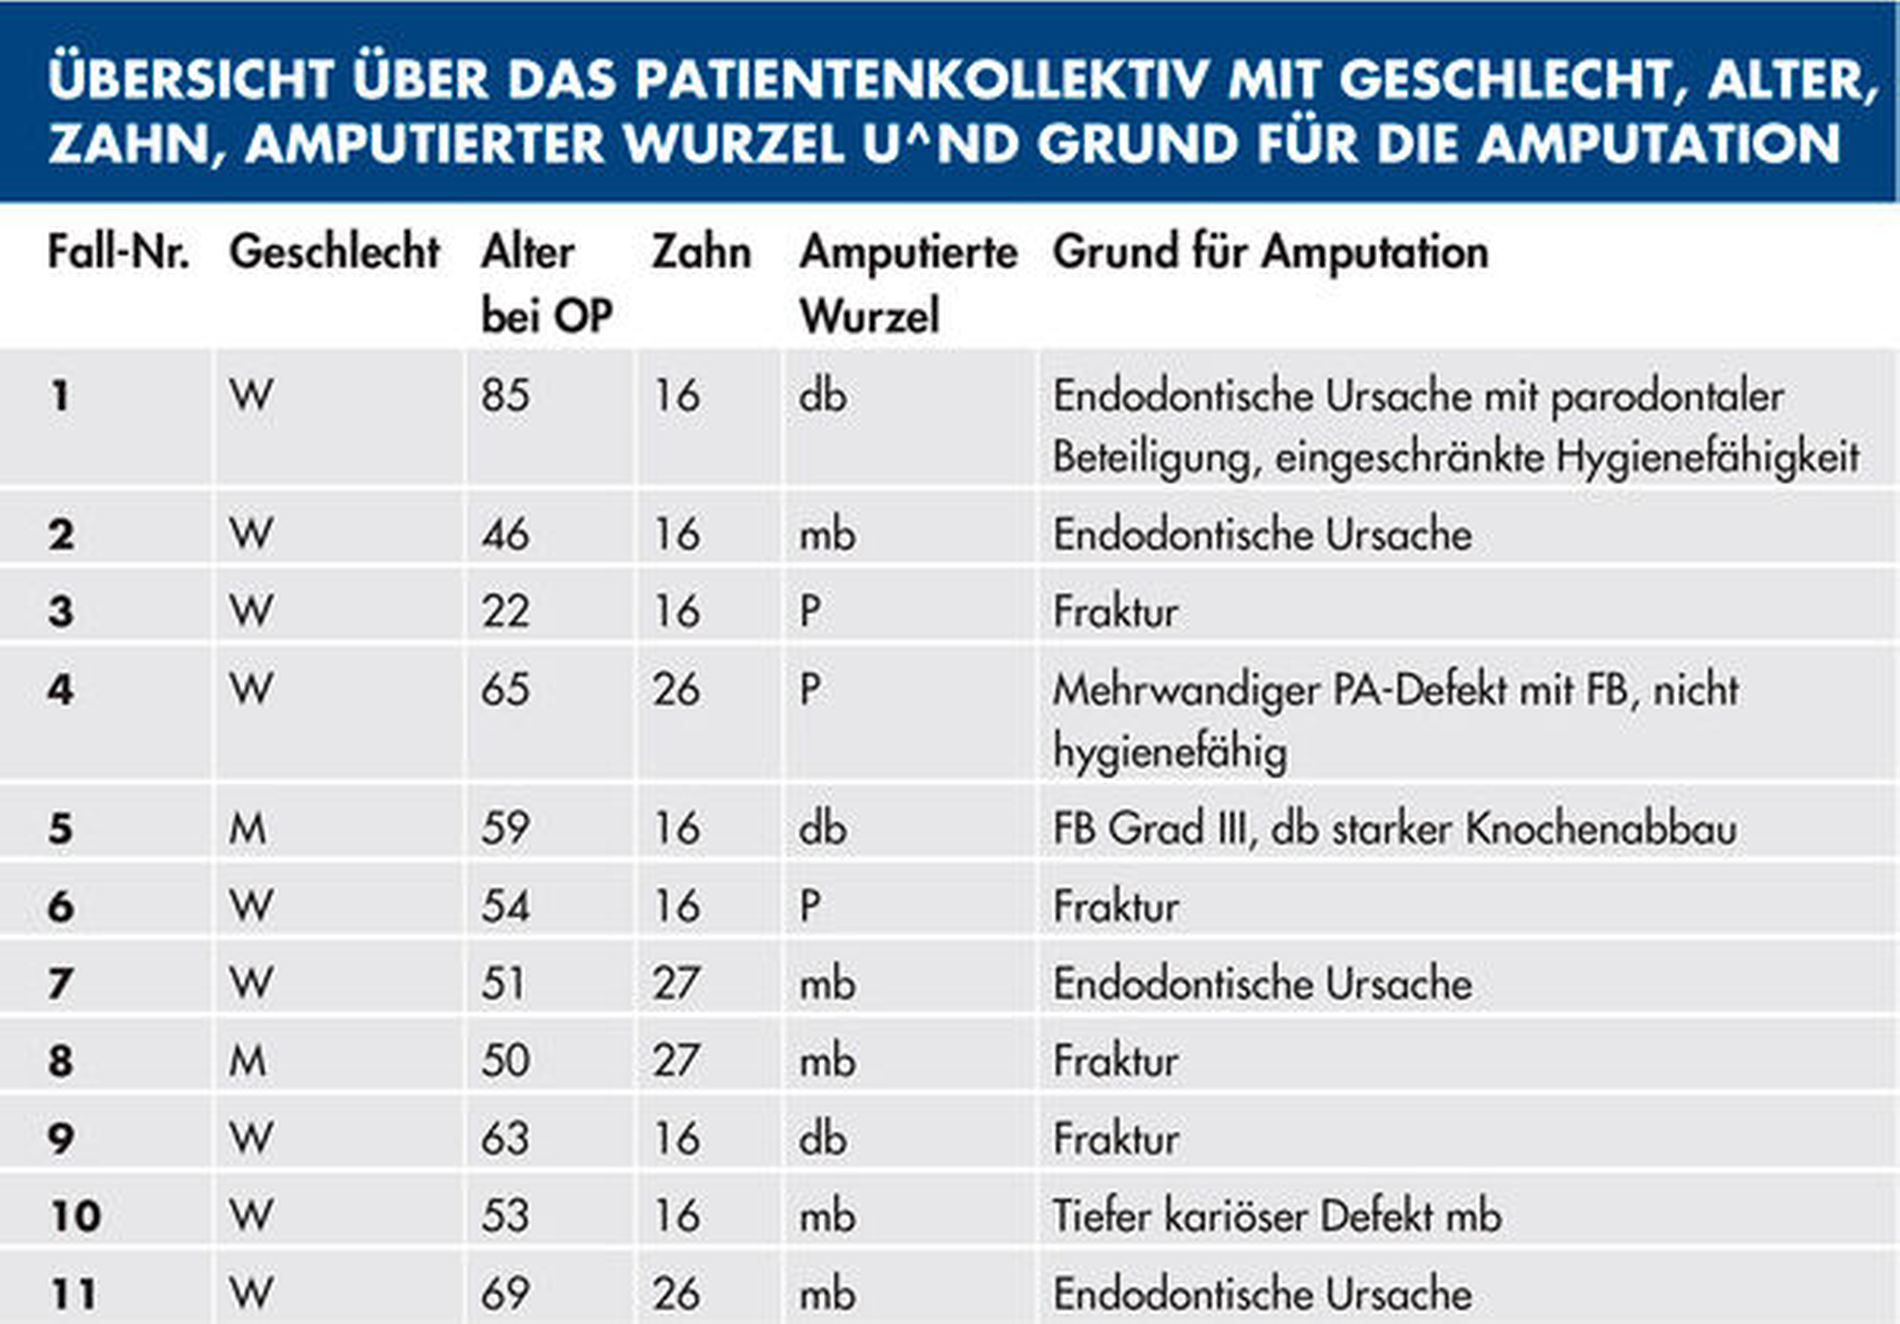

Tabelle 1 (links) zeigt eine Zusammenstellung der in unserer Praxis behandelten elf Patientenfälle mit einer durchschnittlichen klinischen Nachbeobachtungszeit von 47,2 Monaten. Behandelt wurden die ersten und die zweiten oberen Molaren. Das Durchschnittsalter der Patienten lag bei 52 Jahren. Die Nummerierung der folgenden Fallbeispiele entspricht der in der Tabelle.